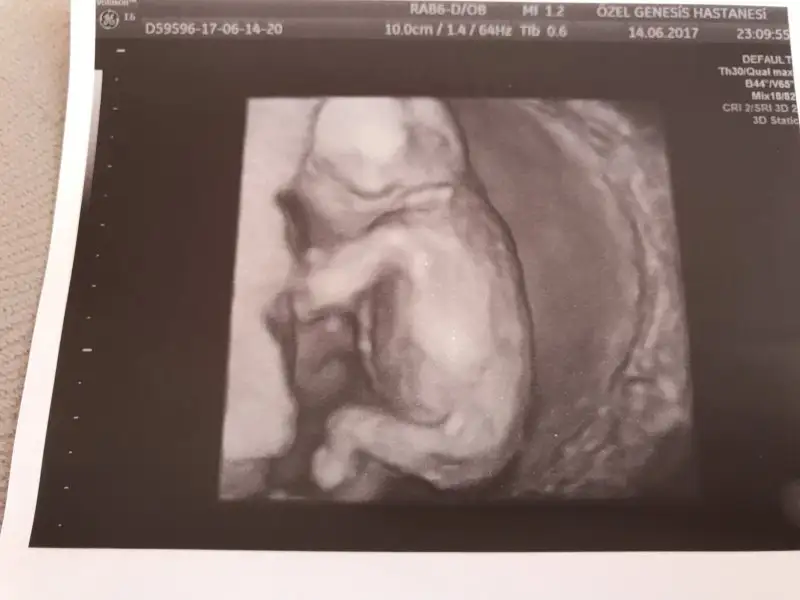

Kızlar merhaba dün gece özel acile gittik 13 +4 günlük hamileyim acilde doktor kız dedi benim randevum haftaya idi kendi doktoruma. Kızım olacak hayırlısıyla tabi haftaya kafa değişir mi bilmiyorum hiç. Bide renkli foto attı bakın bakalım tahminler tuttumu:.) bu arada bebek sırtını dönmüştü nasıl Gördü kız dedi oda aklımda soru işareti